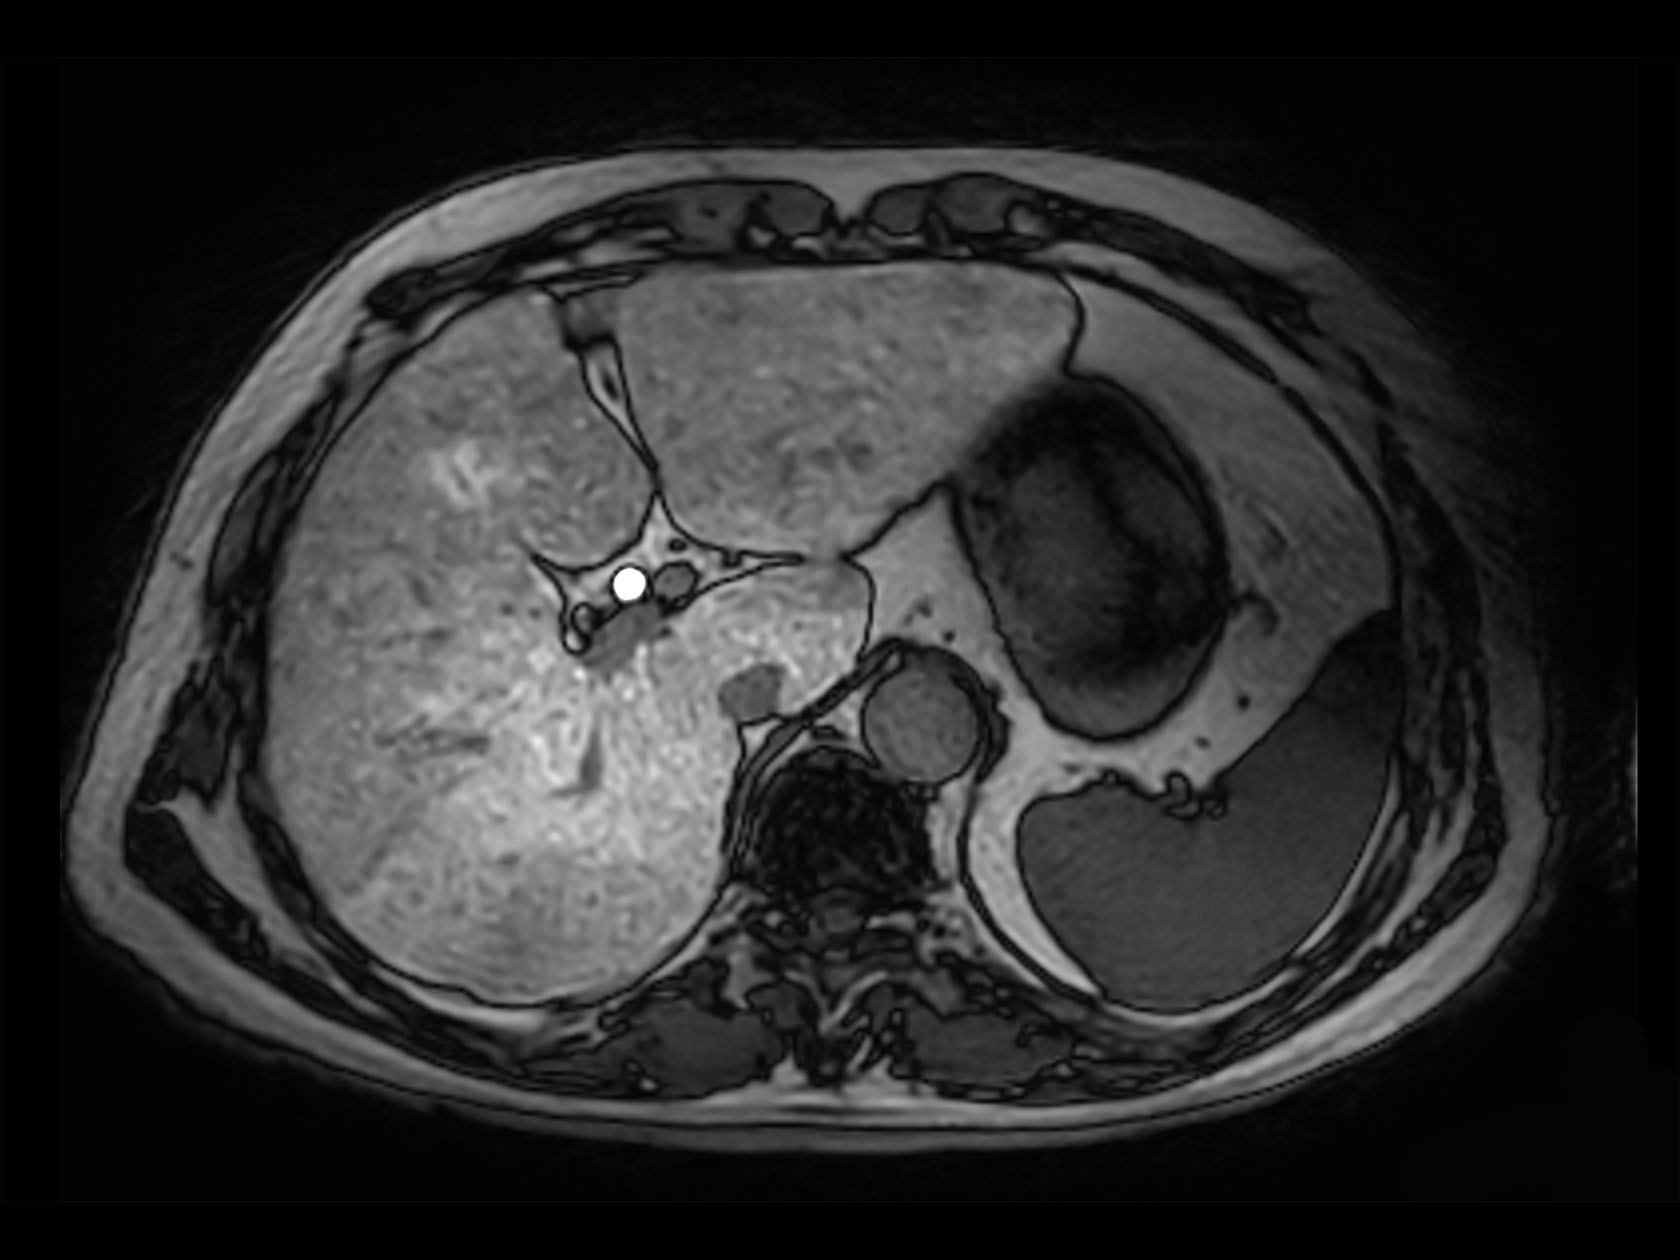

Axial mDIXON XD FFE (Water only)